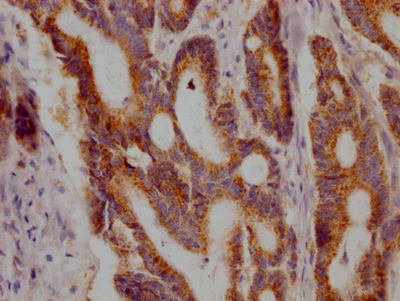

IHC image of CSB-RA227790A0HU diluted at 1:100 and staining in paraffin-embedded human colon cancer performed on a Leica BondTM system. After dewaxing and hydration, antigen retrieval was mediated by high pressure in a citrate buffer (pH 6.0). Section was blocked with 10% normal goat serum 30min at RT. Then primary antibody (1% BSA) was incubated at 4℃ overnight. The primary is detected by a Goat anti-rabbit IgG polymer labeled by HRP and visualized using 0.05% DAB.